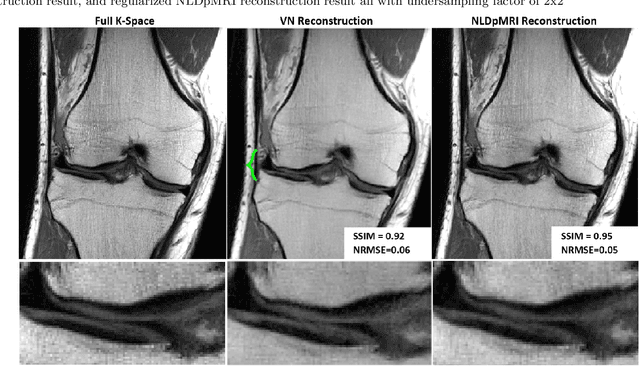

Fast data acquisition in Magnetic Resonance Imaging (MRI) is vastly in demand and scan time directly depends on the number of acquired k-space samples. The most common issues in any deep learning-based MRI reconstruction approaches are generalizability and transferability. For different MRI scanner configurations using these approaches, the network must be trained from scratch every time with new training dataset, acquired under new configurations, to be able to provide good reconstruction performance. Here, we propose a new parallel imaging method based on deep neural networks called NLDpMRI to reduce any structured aliasing ambiguities related to the different k-space undersampling patterns for accelerated data acquisition. Two loss functions including non-regularized and regularized are proposed for parallel MRI reconstruction using deep network optimization and we reconstruct MR images by optimizing the proposed loss functions over the network parameters. Unlike any deep learning-based MRI reconstruction approaches, our method doesn't include any training step that the network learns from a large number of training samples and it only needs the single undersampled multi-coil k-space data for reconstruction. Also, the proposed method can handle k-space data with different undersampling patterns, and different number of coils. Unlike most deep learning-based MRI reconstruction methods, our method operates on real-world acquisitions with the complex data format, not on simulated data, real-valued data, or data with added simulated-phase. Experimental results show that the proposed method outperforms the current state-of-the-art GRAPPA reconstruction method.